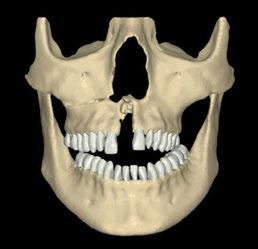

Se presenta un caso de reconstrucción maxilar tras la extirpación de un carcinoma adenoide quístico maxilar izquierdo en una paciente de 35 años. Tras la realización de una maxilectomía parcial es reconstruida de forma inmediata con el colgajo de músculo temporal homolateral. A los 2 años de finalizar el tratamiento radioterápico y sin evidencia de recidiva, se realiza la reconstrucción del maxilar y el proceso dentoalveolar mediante el diseño y fabricación de un implante subperióstico de titanio a la medida del defecto. Es estabilizado con tornillos de osteosíntesis para recuperar el volumen facial y permitir una rehabilitación fija cerámica. Tras dos años de evolución, el caso sirve de ejemplo para discutir la planificación, el diseño, la técnica quirúrgica, las indicaciones y contraindicaciones y pronóstico de los nuevos implantes subperiósticos de titanio.

Reconstrucción del maxilar izquierdo (antes y después).

Para ilustrar el proceso, presentamos el caso de una mujer joven diagnosticada de carcinoma adenoide quístico en la región posterior del hemipaladar izquierdo (Figuras 1 y 2). El procedimiento quirúrgico realizado fue una

maxilectomía parcial que incluyó las piezas 24-26 y desde el reborde alveolar hasta la base del cráneo (Figuras 3 y 4). En este caso, la órbita y el globo ocular pudieron ser preservados. La reconstrucción inmediata se realizó mediante un colgajo de músculo temporal homolateral (Figura 5) y el defecto de la fosa temporal fue cubierto mediante una malla de titanio. Posteriormente, la paciente recibió radioterapia (Figuras 6 y 7). 2 años más tarde se diseñó un IS con anclaje en el arbotante nasomaxilar, zona subnasal izquierda

Figura 1. Imagen preoperatoria de la paciente.

Figura 2. Carcinoma adenoide quístico en región posterior del hemimaxilar izquierdo.

Figura 3. Maxilectomía parcial.

Figura 4. Defecto maxilar tras resección del tumor.